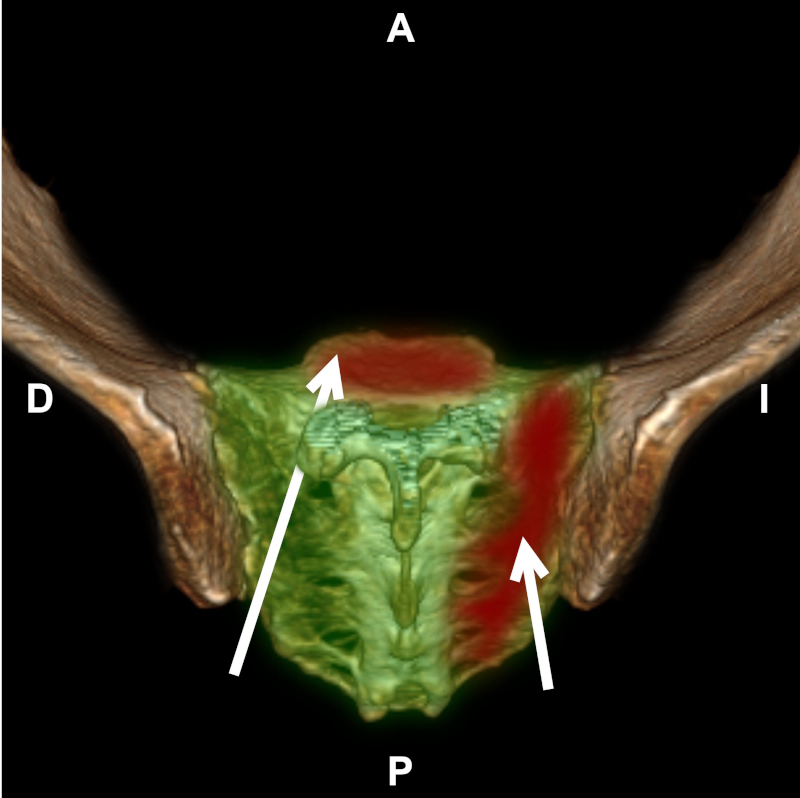

Figura 6

TC con reconstrucción 3D de pelvis, vista posterosuperior. Hueso sacro (verde). Lesiones óseas (rojo) y sus vías de abordaje (flechas).